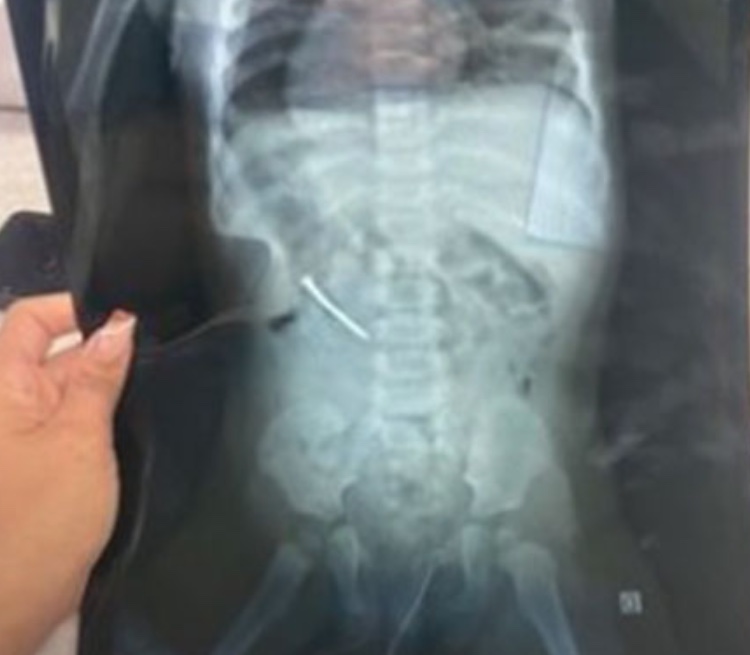

Houve uma tentativa de remoção por endoscopia, mas o prego desceu para o intestino e foi necessário avaliar o quadro. Ontem, a menina foi encaminhada ao Hospital Regional de Marabá, onde um novo raio x detectou que o objeto estaria descendo "de cabeça para baixo", o que facilitaria a saída e diminuiria as chances de perfuração.